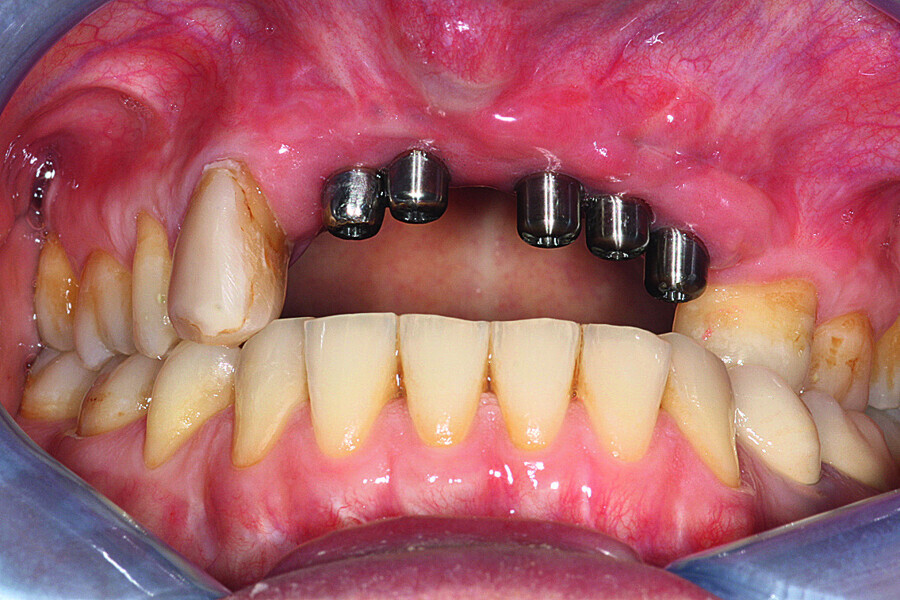

Fig. 3: Examination after three years revealed

a negative short-term prognosis for the implants owing to significant recession at the right implant and hyperplastic tissue.